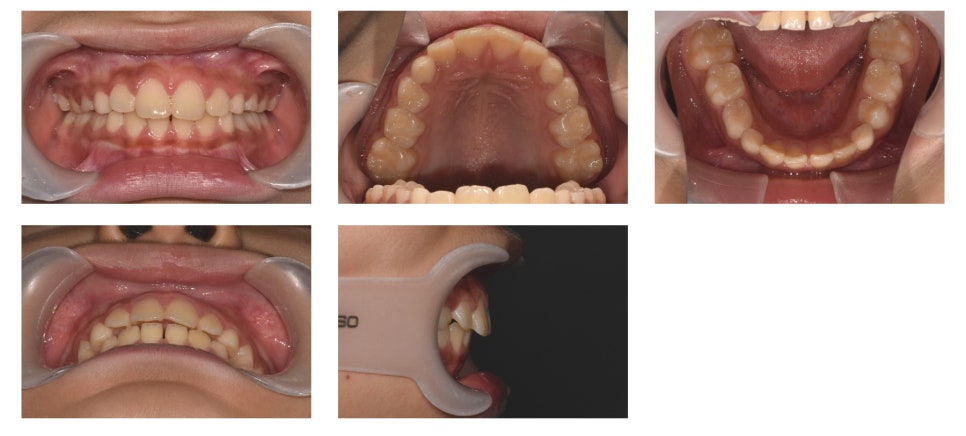

📈 치료 결과

Activator 착용 후 약 1년이 지난 시점, 치료를 종료하였습니다.

치료 전에는 돌출되어 있던 상악 전치부가 눈에 띄게 개선된 것을 확인할 수 있습니다.

무엇보다 환자와 보호자 모두 치료 결과에 매우 만족하셨습니다.

치료시작일 : 2018년 9월 21일, 치료종료일 : 2020년 7월 14일